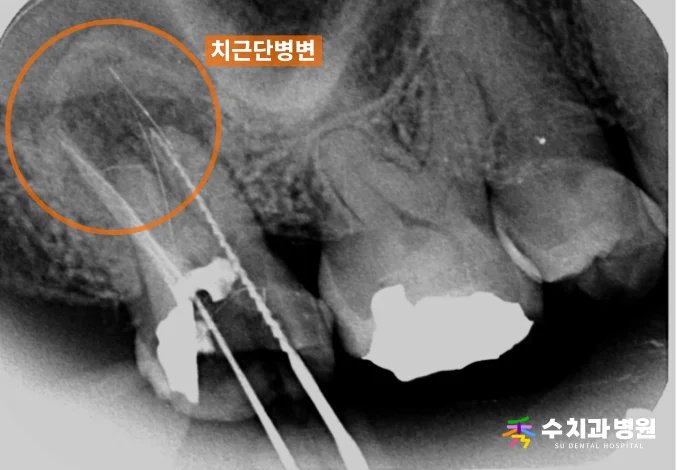

[📸 치료 중 엑스레이] (촬영일: 2023년 8월)

2️⃣ 플라즈마 재신경치료

이후 플라즈마 장비를 활용하여 수 차례에 걸쳐

복잡한 신경관 내부를 꼼꼼하게 소독하고 세척하며,

뿌리 끝 염증을 정밀하게 치료했습니다.